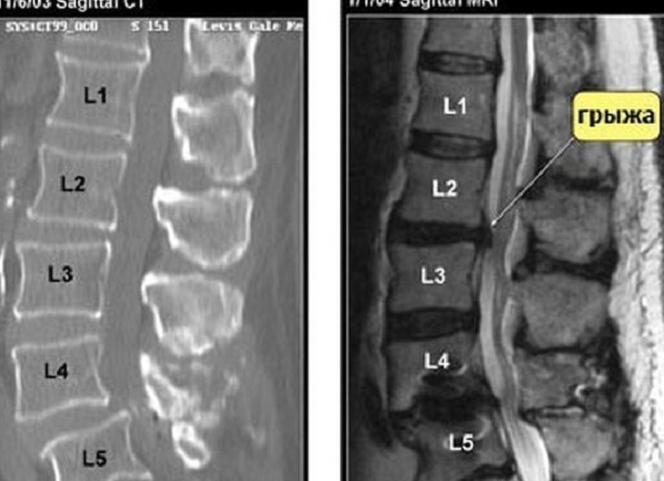

Различие КТ и МРТ в том, что МРТ более четко видит хрящевые и мягкие ткани, кровеносные и лимфатические сосуды и полый кишечник. А КТ является незаменимой для изучения костных образований и кровотечений. Кроме того, довольно заметно различимы воспаления, отложения солей или аномалии в нервных тканях.

Следует отметить также, что МРТ дает максимально точную картину области позвоночника, которая исследуется, поскольку отсутствуют на снимках артефакты костей. Кроме того, определяется отличие тканевых структур на изображениях. При магнитно-резонансной томографии могут устанавливаться изменения биохимических процессов в тканях.

При магнитном исследовании лучше визуализируются мягкие ткани, а вот кости обычно плохо просматриваются, так как кальций не дает резонанс.